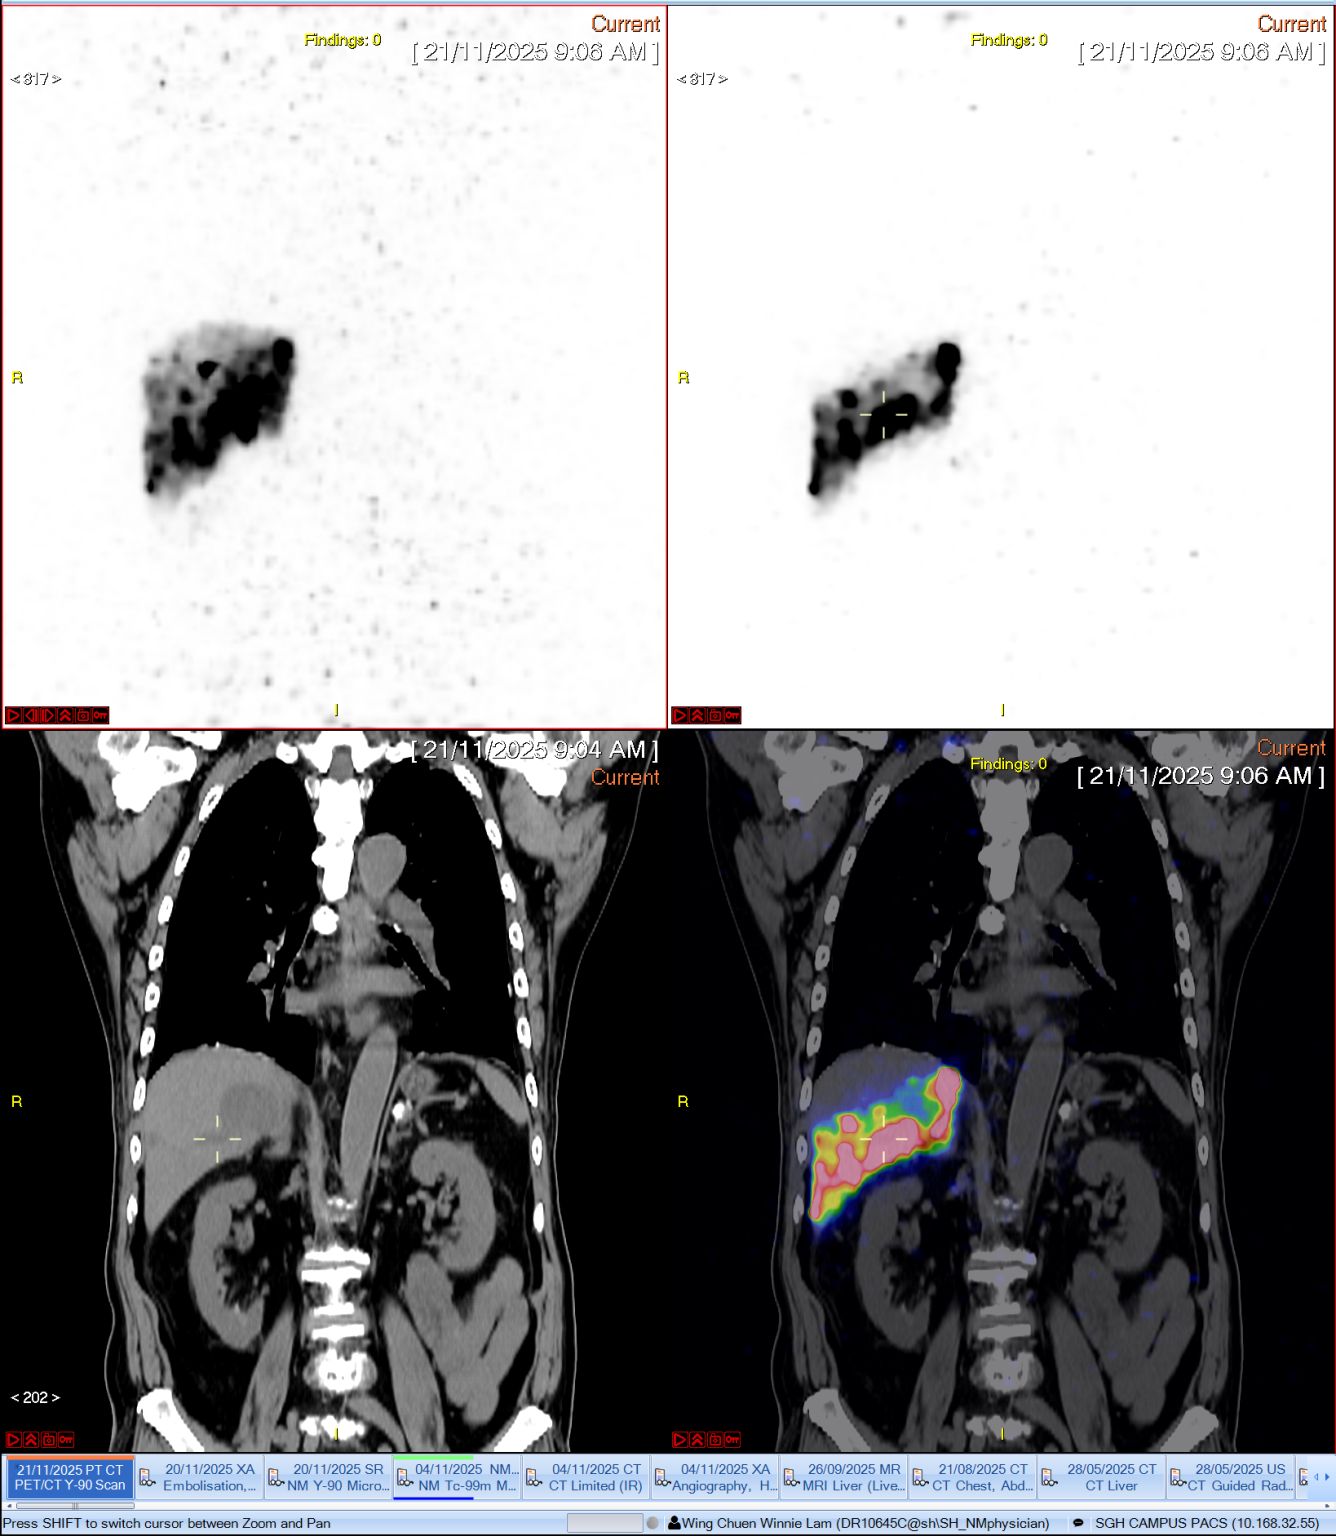

“Ushering in a new era of molecular imaging and precision medicine with state-of-the-art 1.48m long axial field of view total-body PET/CT scanner at Singapore General Hospital.

What used to take close to half an hour on the scan couch for our post Y-90 therapy liver tumour patients can now be done in less than 5 minutes with superb image resolution.”